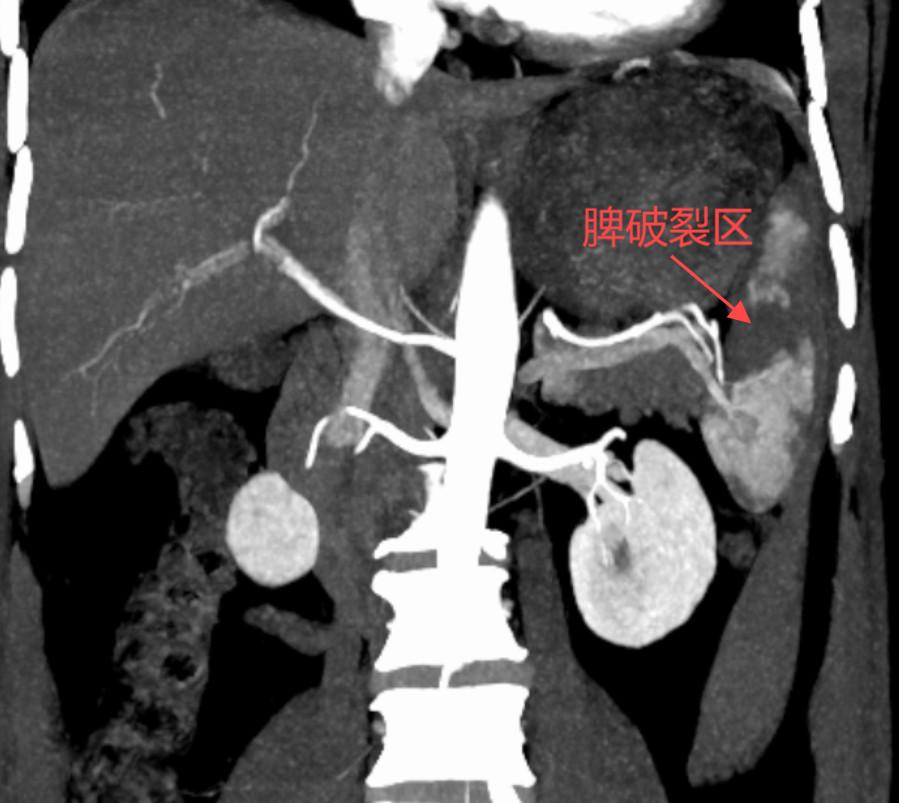

因撞伤导致脾脏破裂和脾脏出血

这波属于“人体血库”炸了

▶ 外伤性脾破裂(Ⅰ-Ⅲ级),脾蒂大血管未受损,脾脏无广泛挤压伤;